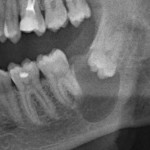

Это мой самый любимый и тщательно подготовленный проект — семинар по немедленной имплантации. Он уже дважды был в Москве, и однажды — в Нижнем Новгороде. На этот раз, мы проводим его совместно с компанией APEX в Санкт-Петербурге, и посвящен он будет… догадайтесь с трех раз?))) Через фокус немедленной имплантации будут рассмотрены различные имплантационные системы, операции остеопластики, синуслифтинга, удаления зубов и превентивной аугментации лунок.